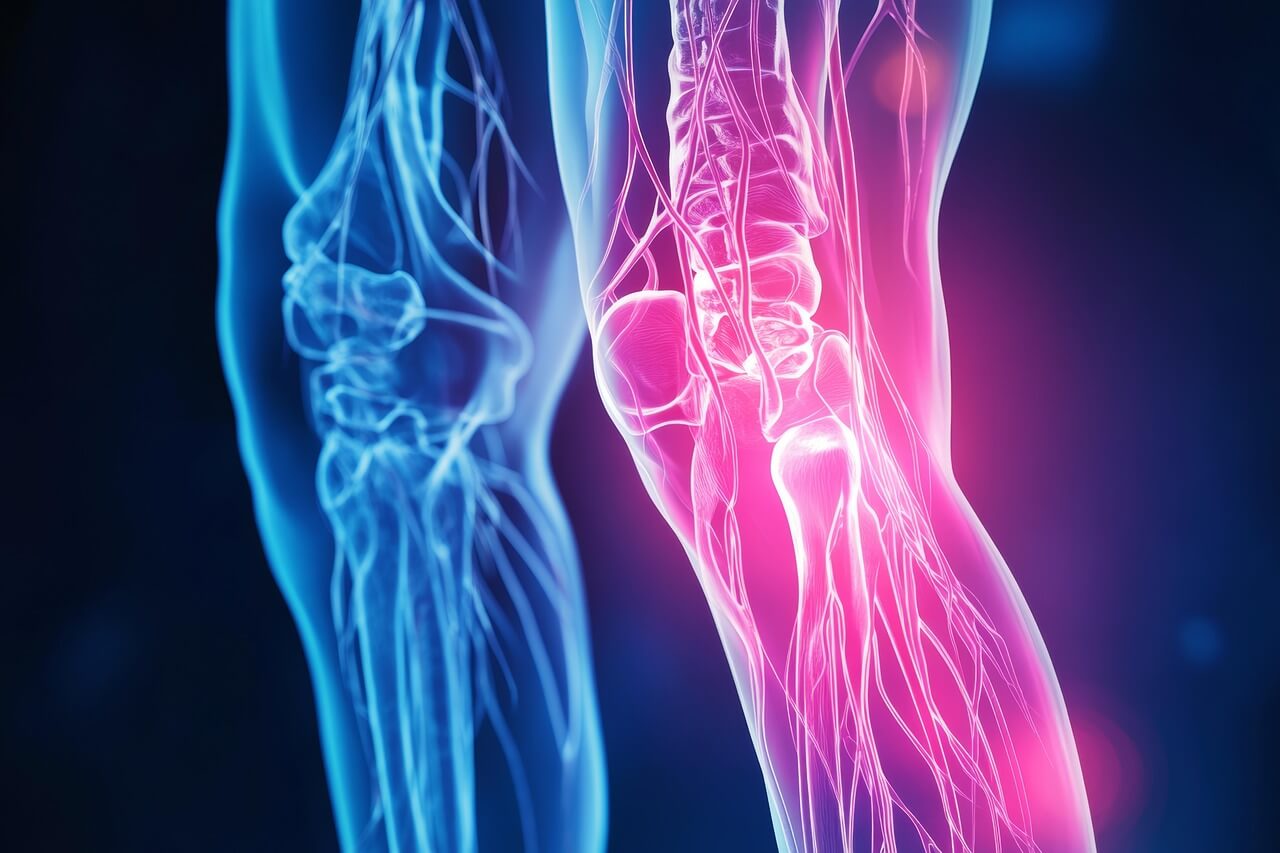

무릎 관절 통증이란 무엇인가요?

무릎 관절 통증은 연골 손상, 관절염, 반월상 연골판 파열, 인대 손상 등 여러 원인으로 발생하는 증상입니다. 일상에서 걷기, 계단 오르내리기, 앉았다 일어설 때 통증이 심해집니다.

무릎 관절 통증의 주요 원인

- 퇴행성 관절염(골관절염) — 연골 마모로 발생.

- 반월상 연골판 손상 — 운동 중 갑작스러운 회전으로 발생.

- 인대 손상(전방십자인대 등) — 외상성으로 통증과 불안정감 유발.

- 슬개골 연골연화증, 활액낭염 등 — 과사용 또는 비대칭 하중으로 발생.